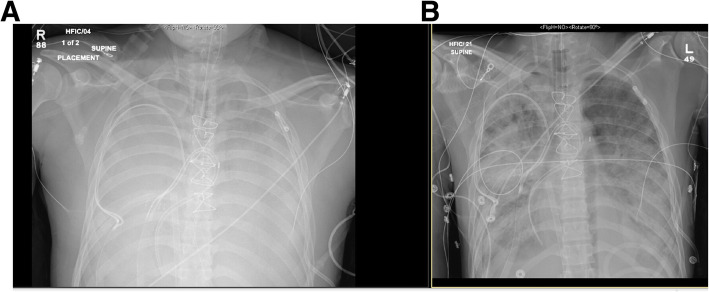

He had no clinical history of inhalational injury other than the vaping exposure. He had severe progressive refractory respiratory failure despite maximal ventilatory strategies with a progressive increase in airway pressure and dropping Pa02/Fi02 ratio. At this time, he became hypotensive and was vasopressor dependent. Treatment was started with vitamin C, thiamine, hydrocortisone and multiple antibiotics (vancomycin, cefepime, azithromycin and doxycycline) for concern of sepsis as well as oseltamivir for Influenza A. Despite antibiotic treatment, his hypoxic respiratory failure further progressed and he required aggressive ventilatory support with a positive end-expiratory pressure (PEEP) of up to 30. The patient’s Pa02/Fi02 ratio was only 37 when the extracorporeal membrane oxygenation (ECMO) team was contacted and a bilateral femoral veno-venous (V-V) ECMO was placed at the spoke institution as part of our mobile ECMO program and patient was brought to our hub institution. After the procedure he was stable enough to be transferred to our facility. Despite the V-V ECMO, the patient required multiple vasopressors and although his lactic acid decreased initially, there was a progressive need for escalatory support and patient was converted patient from V-V ECMO to veno-arterial (V-A) ECMO. Given severe sepsis with shock, the peripheral V-A ECMO was deemed to be insufficient to provide hemodynamic support, and he was subsequently placed on central V-A ECMO to improve end-organ function. The patient’s clinical course was complicated by acute kidney failure for which he required dialysis, liver failure and encephalopathy which was likely secondary to his metabolic derailment and sepsis. He also experienced multiple episodes of atrial fibrillation with rapid ventricular response for which he was successfully cardioverted three times. A transthoracic echocardiogram showed a severely dilated right ventricle as well as biventricular systolic dysfunction. Due to a worsening pulmonary edema, he was emergently placed on an intra-aortic balloon pump (IABP). Although the CXR showed subsequent improvement in aeration with improvement in minute ventilation on the ventilator (Fig. 3), the patient also developed severe limb ischemia with skin mottling and ecchymoses on his extremities, trunk, nose and ears. Sepsis and cytokine storm with severe vasoplegia requiring vasopressors were determined to the ongoing issue. Severely diminished tibial flow and thrombi in the bilateral posterior tibial arteries was seen on vascular ultrasound and out of concern for compartment syndrome the patient underwent a fasciotomy. During this time, patient was awake, alert and communicative with the family at the bedside. Despite our best efforts, non-viable muscle was seen in all four compartments bilaterally and a bilateral through-knee amputation was performed. Confronted with the patient’s poor prognosis, the family decided to suspend life-supporting measures in favor of transition to comfort care. The patient expired shortly after the IABP and ECMO were turned off. In total, the patient spent two weeks in the hospital. The family consented to an autopsy.